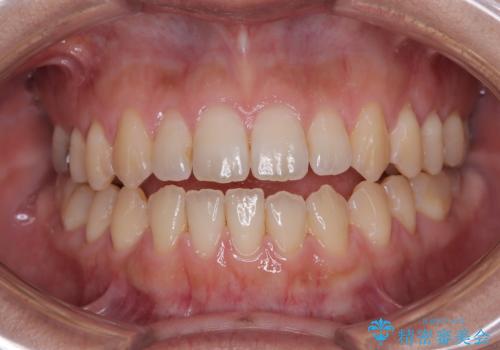

【モニター】食事が取りづらい 極端な開咬をインビザラインで解決

- 極端な開咬を気にして来院された患者様です。

開咬の方の特徴として、幼少期の指しゃぶりの癖や、強い舌の突出癖が挙げられます。

こちらの患者様も強い舌の突出癖が認められたため、矯正治療を行うにあたり、舌のトレーニングをしっかりと行っていただくように指示をいたしました。

開咬はインビザラインが得意とする歯列不正であるため、舌のトレーニングを行いながら、インビザラインにて矯正治療を行うこととしました。

担当医としては、もっと上下の前歯を接触させるところまで治療を進めたいという思いがありますが、今まで咀嚼できなかったものが食べられるようになったということで、この状態で治療終了となりました。